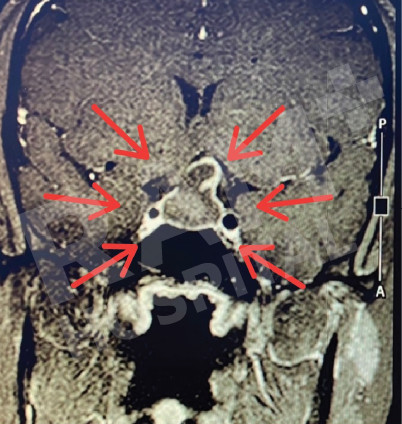

磁共振成像(MRI)可清晰、细致地显示垂体的异常病变,精准定位垂体腺瘤的位置;结合静脉造影增强检查,还能明确腺瘤的具体位置与病变性质,同时清晰呈现脑部周边组织及鼻窦的情况。这一项检查结果可为制定诊疗方案、随访评估垂体腺瘤的治疗效果,乃至规划手术方案提供明确、可靠的依据。

| 术前 | 术后 |